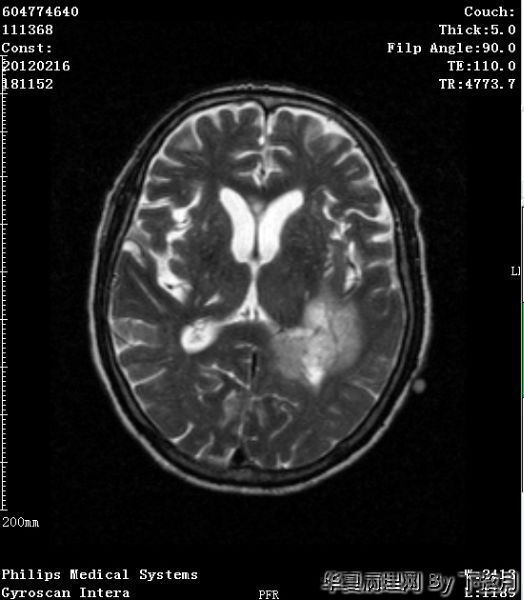

左侧颞叶及胼胝体膝部占位图3

名称:图3

描述:HE 100倍-2

粘液型乳头状室管膜瘤:好发于年轻人,几乎毫无例外位于圆锥-马尾终丝区。组织学Ⅰ肿瘤细胞围绕血管粘液样间质为轴心,排列成乳头状为特点。本例是老年人,位于左侧颞叶及胼胝体膝部,年龄和位置不太相符。另外本例Ki-67指数有点高。有点疑惑

从图1可见肿瘤似位于脑皮质外围,有粘液背景,部分如脊索瘤样,倾向于脊索瘤样脑膜瘤。